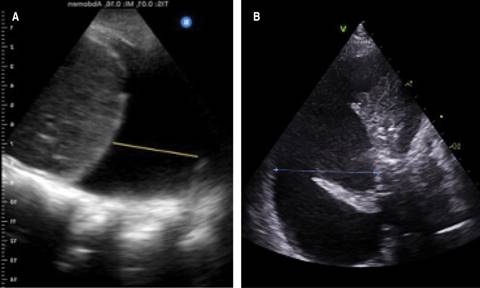

Regarding the etiology of the pleural effusion, ultrasound does not allow sufficient discrimination in the different etiologies and the compositions of the effusion. The sonomorphological characteristics may vary depending on its nature, cause, and chronicity. The appearance of the pleural fluid can be divided into four patterns: (1) anechoic (Figure 1A), (2) non-septated complex (defined by the presence of particles within the pleural fluid) (Figure 1B), (3) septated complex (defined by the presence of septa and fibrin in the pleural fluid) (Figure 1C), and (4) homogeneously echogenic («bright» pleural effusion) (Figure 1D), the last being the most common in hemothorax and empiema.6

Figure 1: A) Anechoic pleural effusion, suggesting transudate. B) Non-septated complex pleural effusion. C) Septated complex pleural effusion. D) Homogeneously echogenic pleural effusion. B-D) Correspond to exudate.